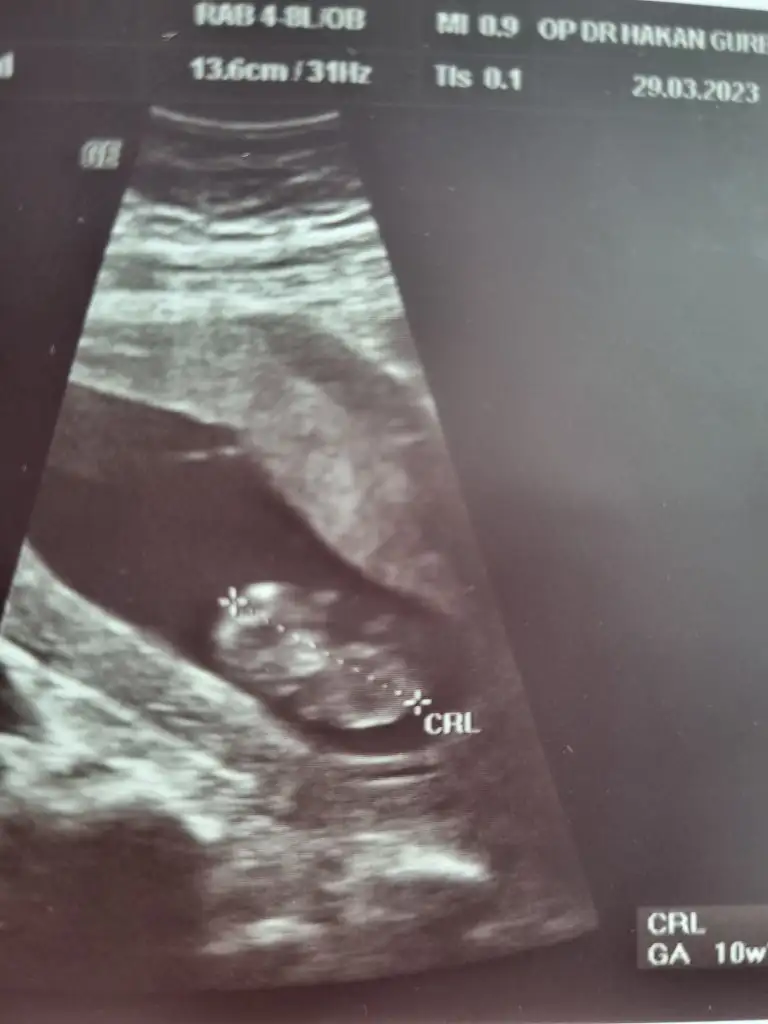

Papatyamaviss Papatyamaviss benim de mi belli olmaz.. ekledim en uygun foto bu 10.hafta bugüne ait

• 16800929872148500445775044353857.webp

16800929872148500445775044353857.webp

19,5 KB · Görüntüleme: 65